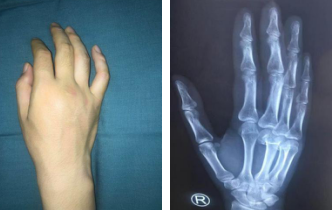

前不久,安徽一名姓刘的男性患者,在结束了一天的工作之后回到家中,身体非常疲惫,因孩子吵闹,一气之下一拳打到墙上,随即右手出现肿胀,疼痛,但他未重视。第二天早上醒来后,刘先生发现自己右手肿胀更加明显,疼得受不了,便到家附近的医院就诊。在医院拍片显示其右手第三、四掌骨颈骨折,断端移位。

术前

于是,刘先生辗转来到我院,正逢手外二熊祖国医生坐门诊。熊医生看完片子,告诉他可以微创手术,而且术后手功能基本恢复正常。刘先生一听很高兴,希望能尽快安排手术。熊医生为其采用的治疗方案为闭合复位经皮微创克氏针内固定,既能很好地固定骨折,还不留疤痕,早期通过功能锻炼,达到恢复功能。熊医生和吴衡医生团队很快做完了手术,术后第二天刘先生就出院了。

熊医生介绍,刘先生术前右手不能握拳,伸不直,伸屈都有影响,术后功能基本恢复正常。